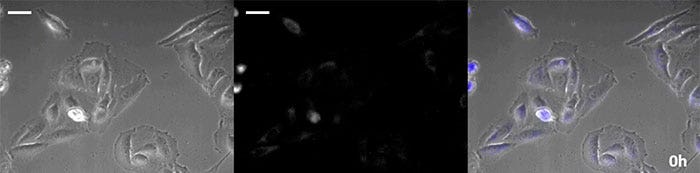

明场图像

发光图像

重叠图像

发光图像伪色(绿色)

视频1。组胺刺激引起的钙离子波动的发光观察(比例尺:500 µM)

腔肠素型的荧光素具有特别高的亮度,但由于它在短时间内就会在细胞中氧化,因此及时补充对于长期观察应用至关重要。为了解决这个问题,我们用高强度发光蛋白灌注了细胞,同时用自动基质添加装置自动添加了腔肠素,以便可以持续监测发光。因此,我们结合使用相衬成像成功地对发光图像进行了超过24小时的监测(图4)。

0小时

图4-1 0小时